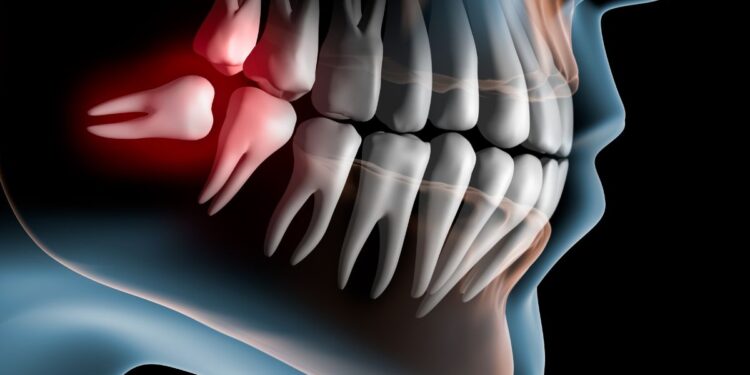

La extracción de las cordales, también conocidas como muelas del juicio, suele considerarse un paso importante dentro de algunos tratamientos odontológicos, especialmente en ortodoncia. Sin embargo, la realidad es que no siempre es necesario extraerlas, pues todo depende de la posición de las piezas, el espacio disponible en la boca y el plan de tratamiento diseñado por el especialista.

- Impacto en el espacio dental: En ciertos casos, las cordales pueden ayudar a proporcionar el espacio necesario para corregir el apiñamiento dental durante la ortodoncia. No obstante, cuando erupcionan en una posición inclinada, ejercen presión sobre los demás dientes y generan movimientos indeseados, comprometiendo los resultados del tratamiento.

El procedimiento comienza con un diagnóstico clínico y radiográfico que permite al odontólogo evaluar la posición exacta de las muelas del juicio. A partir de esta evaluación se define el plan quirúrgico.